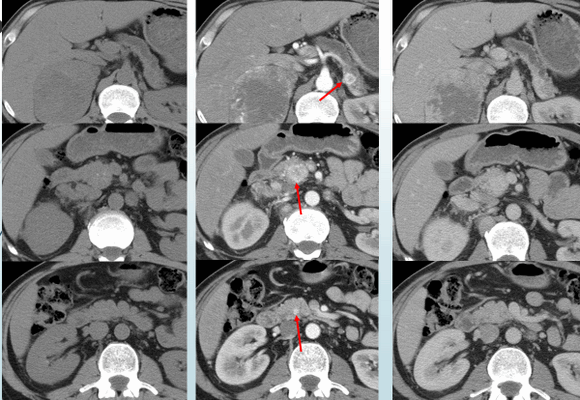

Рисунок 1. Множественные нейроэндокринные опухоли поджелудочной железы. Определяются только на фоне внутривенного введения контрастного препарата.

3. КТ при карциноиде (карциноидной опухоли):

• Подслизистые опухоли:

о Солитарные или множественные, четко отграниченные, накапливающие контраст:

- 80-95% карциноидных опухолей-гиперваскулярные

о Объемное образование в стенке, усиливающееся при контрастировании, лучше визуализируется при дополнительном приеме воды в качестве контрастного вещества

о Первичную опухоль выявить сложнее, чем вторичные очаги

• Распространение опухоли тонкой кишки в брыжейку:

о Объемное образование в брыжейке неоднородной структуры, возникающее вследствие прямой инвазии или метастатического поражения лимфоузлов

о Вплоть до 70% случаев в образовании брыжейки обнаруживаются кальцинаты

о Возможна также деформация, фиксация, ретракция петель тонкой кишки:

- Обусловленная фиброзом брыжейки и десмопластической реакцией

- Десмопластическая реакция проявляется пальцевидными выпячиваниями от образования в прилежащую брыжейку

о Возможно также обрастание и сужение брыжеечных сосудов

о Обструкция тонкой кишки может быть обусловлена новообразованием в ее просвете, перегибом или инвагинацией

• Метастазы в печени:

о В артериальную фазу характеризуются интенсивным контрастным усилением вследствие высокой васкуляризации

о В отсроченную фазу могут быть изо- или гиподенсны по отношению к паренхиме печени

5. Рекомендации по визуализации:

• Мультипланарная КТ с контрастным усилением (или МРТ) с заполнением тонкой кишки водой:

о Артериальная фаза (приблизительно на 35 секунде) и венозная фаза (после - 70-секундной задержки)